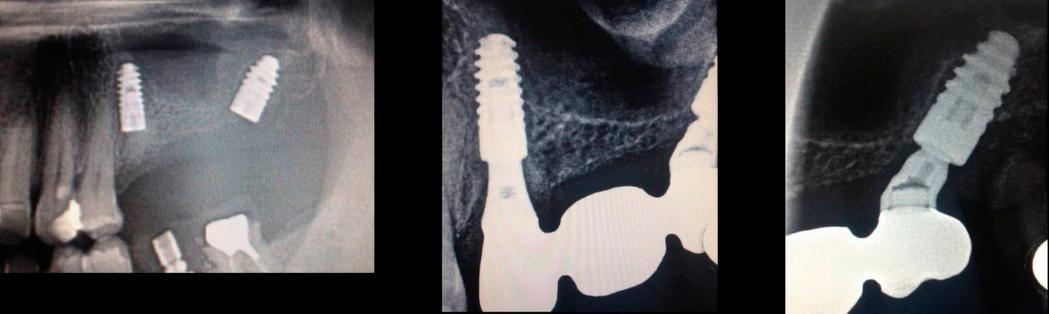

Examples of successful immediate implant placements followed by prosthetic restoration are shown in the images below. As can be seen, the angled implants also integrated well and the restoration is sound.

An example of restoration on implants placed immediately after tooth extraction. YouTube/ Dr. Sergey Rozhnov /sergiodontolog

While contraindications to immediate implantation exist, they are relatively rare. Angled implant placement also deserves special attention. Although the load is distributed unevenly and the abutment and retention screw experience greater stress compared to axial placement, an angled implant allows the clinician to: